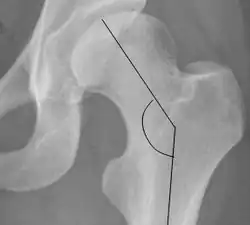

| Cervical diaphyseal angle |

|

The angle formed between the femoral neck and femoral diaphysis | 120° to 140°